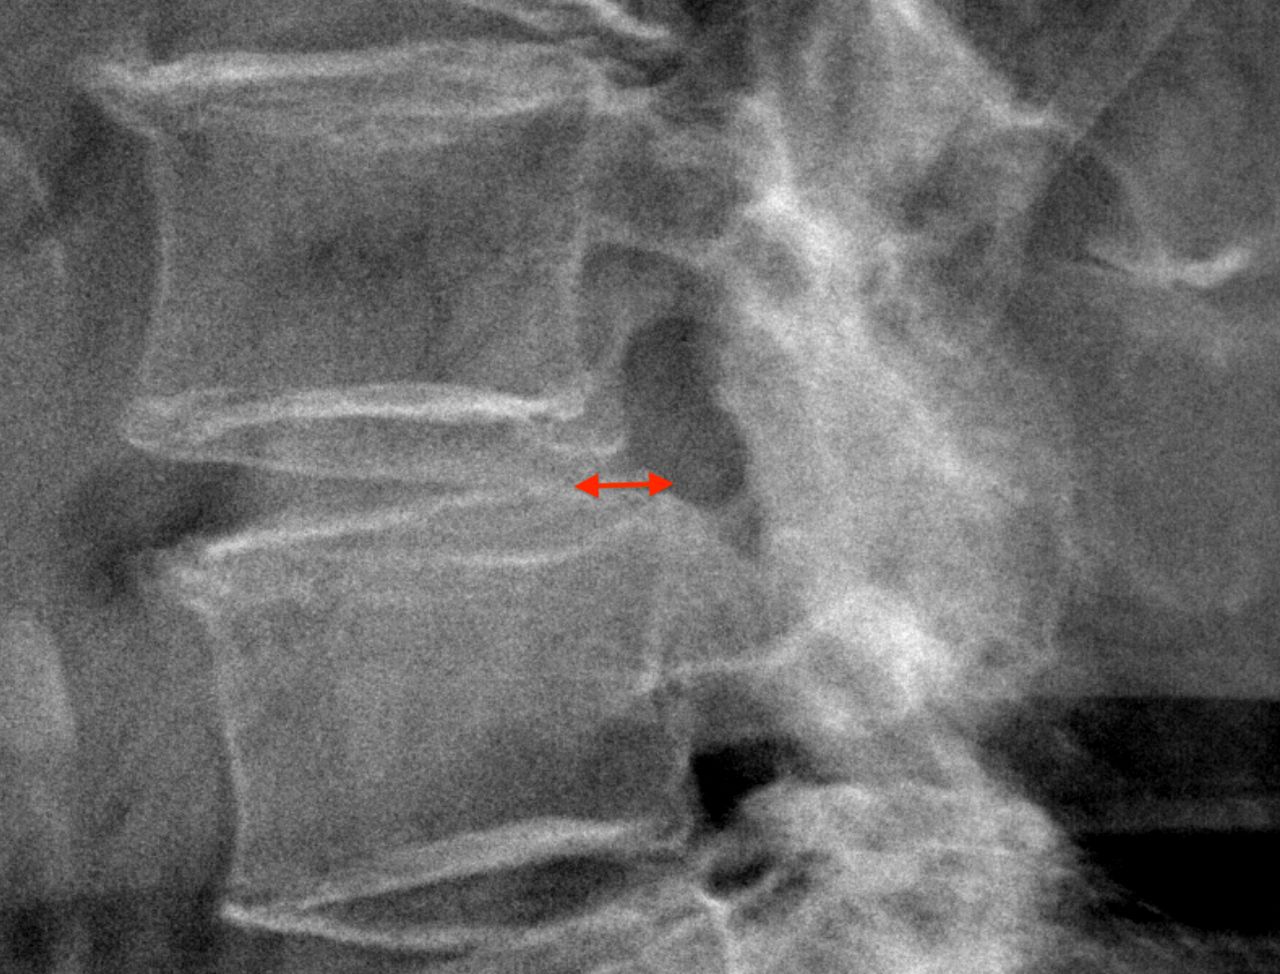

• stenosi del canale vertebrale cervicale e lombare;

• spondilolistesi cervicale e lombare;

• malattie infiammatorie croniche, come l'artrite reumatoide, la spondilite anchilosante, la sindrome di Forestier, l'ossificazione del legamento longitudinale posteriore, l'ossificazione del legamento flavo.